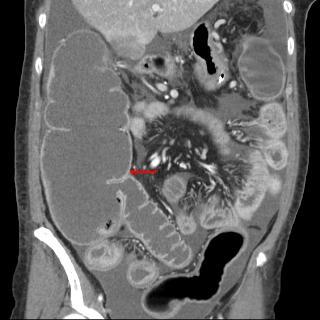

Occlusion du colon a cause

est hyper-dense a bord irregulier (fleche rouge )

Le colon en aval est collapse . |

Meme cas en coupe axiale .

droit |